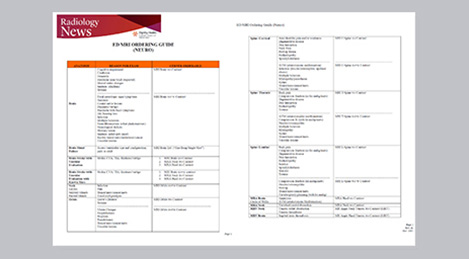

Guidance on appropriate use of MRI

A range of protocol sheets was developed to help ensure that referring physicians order the most appropriate MRI exam. The optimized MRI protocols also include 3D contrast-enhanced imaging, allowing neurosurgeons to comfortably use the isotropic data in the operating room while performing stereotaxic surgery.

Targeted scanning is important

The ED physicians can only request exams from a selected set of available exam protocols – as represented on the protocol sheet – minimizing the time necessary for the MRI scan. The sheet contains advice as to which scan to order (i.e. MRI vs. CT, contrast vs. non-contrast) depending on the situation, and encouraging physicians to order targeted scans. Even though the process has now been implemented, education still remains important; new neurology residents, for example, are informed as to the use of the ED MRI scanner, how it’s being utilized, and the importance of targeted scanning. “In my opinion, education has been crucial to establish the MRI exam as an ED test,” says Dr. Karis. “This is really key. If you can’t establish this concept, then you can’t convert everyone to the mindset that this is an ED test.”